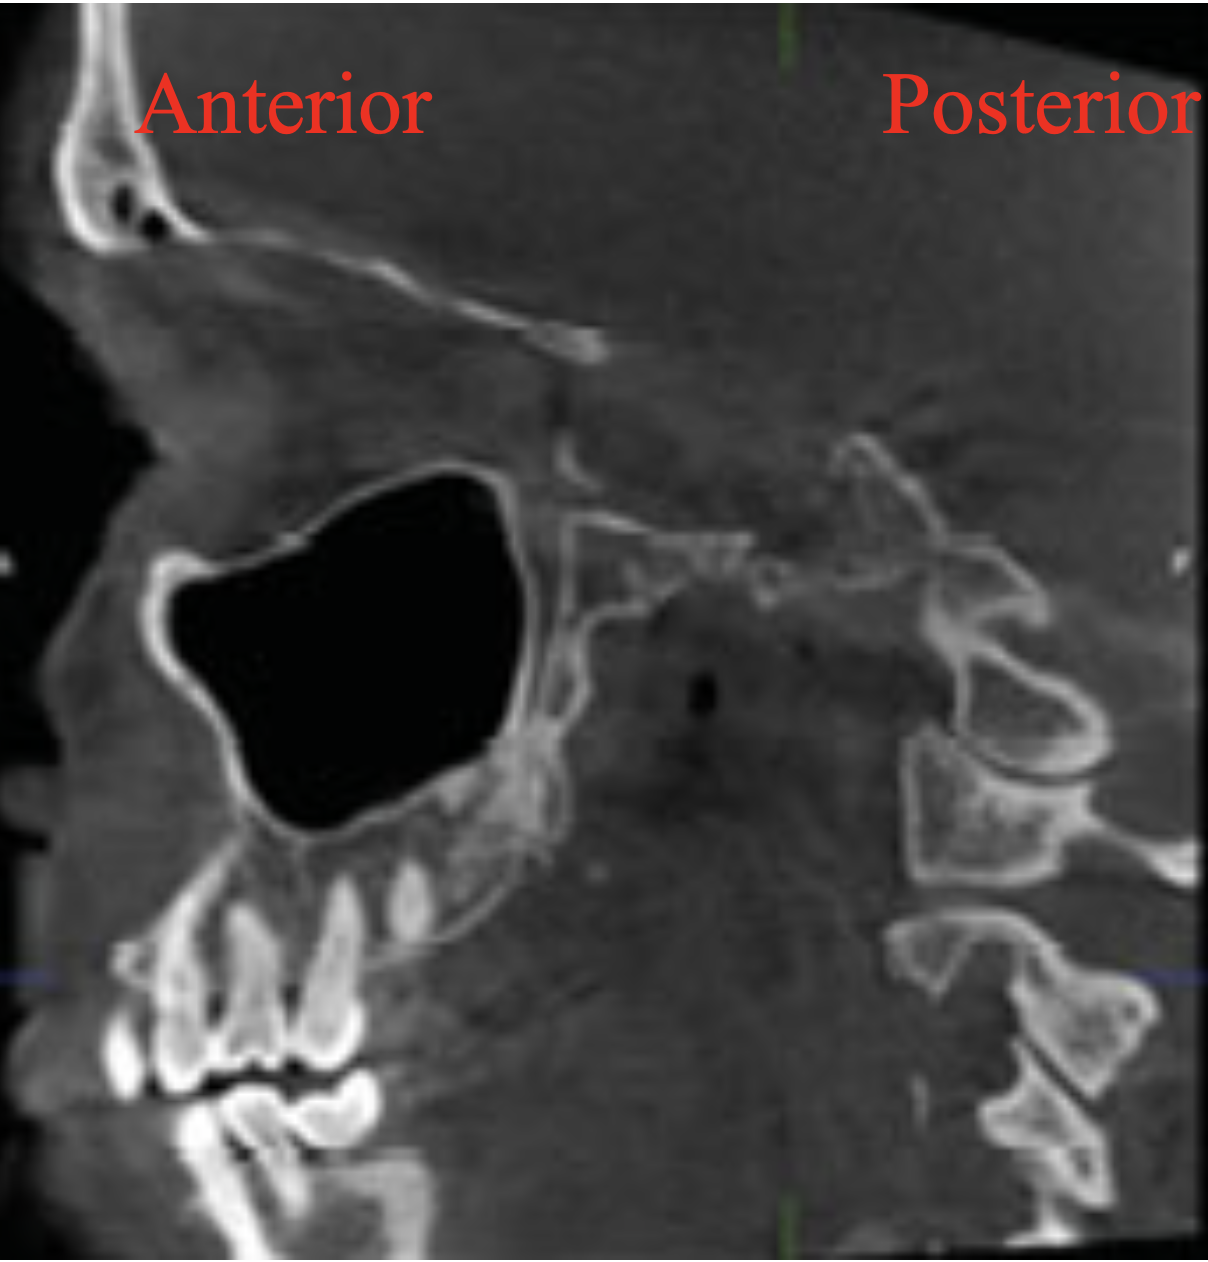

Q

A

Coronal